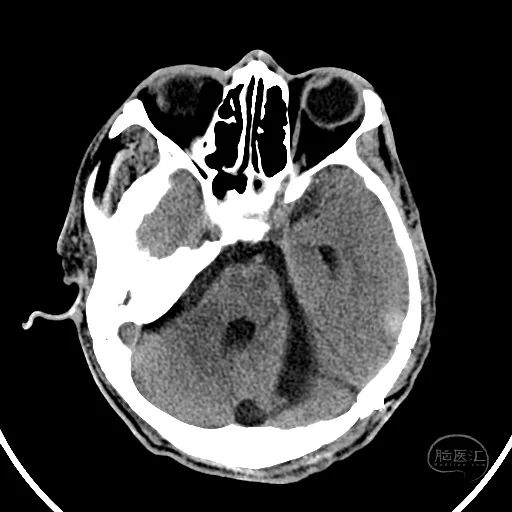

术后第一天复查CT显示后颅窝血肿清除,第四脑室隐约可见。

患者昏迷状,GCS评分3分,双侧瞳孔等大等圆,直径3mm,对光反射迟钝。

额叶血肿清除后,水肿明显。

额叶残余少量血肿,脑室引流管在位。

骨窗见枕骨大孔开放。术中清理枕骨大孔骨折时,无明显出血。